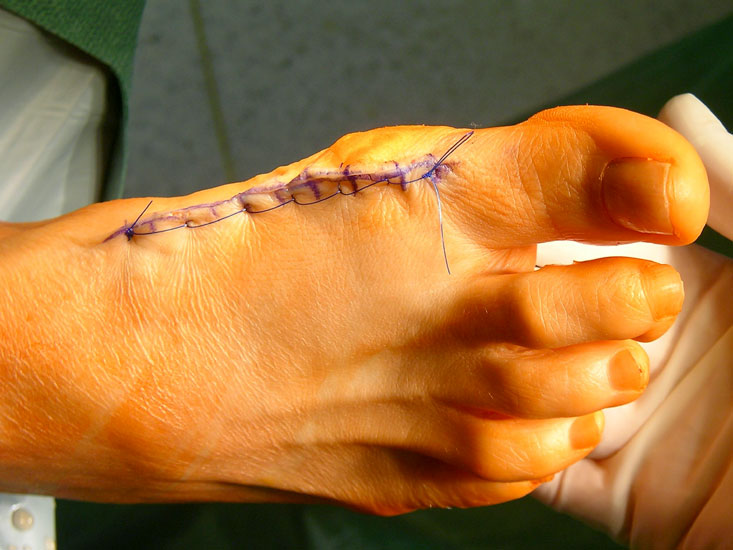

Zum Lesen der Bildbeschreibung und Vollansicht bitte die Bilder anklicken.

• Erster Verbandswechsel am Tag nach der Operation, bei normaler Wundheilung danach alle 2-3 Tage.

Die basisnahe Crescentic Osteotomie gehört zu den Standardeingriffen zur Korrektur fortgeschrittener Hallux valgus Fehlstellungen. Ein distaler Weichteileingriff sollte routinemäßig mit durchgeführt werden. Die Mobilität des ersten Strahls wird auf ein normales Maß reduziert und ermöglicht wieder eine normale Lastaufnahme 1. Der Intermetatarsale Winkel wird gut korrigiert. Die Verwendung einer winkelstabilen Plattenosteosynthese zur Fixation einer proximalen Osteotomie am MT I hat sich bereits bewährt894. Häufig wird additiv eine Akin Osteotomie durchgeführt. Irritationen über der tastbaren Platte führen in vielen Fällen zur Metallentfernung.